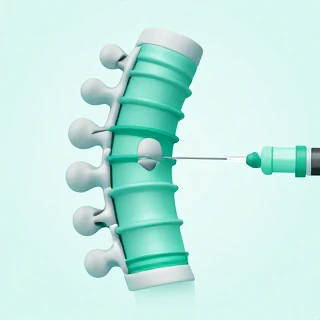

کیفوپلاستی (تزریق سیمان به مهره) + مزایا، کاندید و هزینه | راهنمای کامل

کیفوپلاستی (تزریق سیمان به مهره)؛ نجات ستون فقرات بدون جراحی باز شکستگی مهره بهخصوص در افراد مبتلا به پوکی استخوان میتواند درد شدید و ناتوانکننده